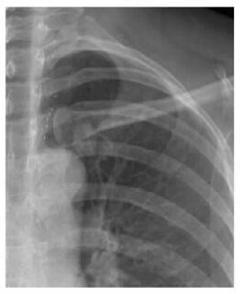

案例二:

圖二 左鎖骨重疊致密結(jié)節(jié),誤為衣服紐扣,病理肺腺癌

案例解析:

該病例發(fā)生在國(guó)內(nèi)某基層醫(yī)院,病患首先通過(guò)胸片攝影篩查,顯示出左上肺野內(nèi)帶高密度橢圓形結(jié)節(jié),由于形狀與紐扣極為相似,誤為衣服紐扣,并未做進(jìn)一步診斷。第二年之后,病患再來(lái)復(fù)查,卻發(fā)現(xiàn)照片上結(jié)節(jié)影增大,立即進(jìn)一步診斷檢查,最終經(jīng)過(guò)活檢證實(shí)為肺癌,錯(cuò)過(guò)了最佳的肺癌治療期。